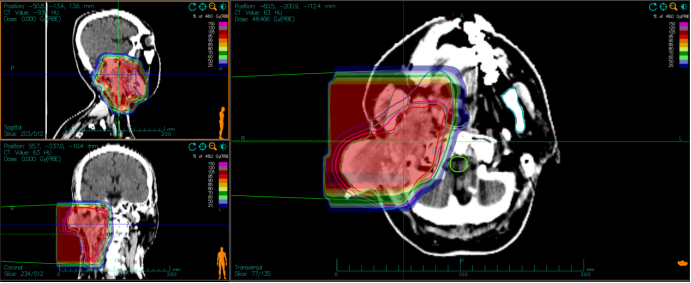

5例患者均完成了碳离子治疗,目前平均随访期15.8个月(13.0-20.0个月),随访至12个月时,1例达到CR,3例达到PR,1例上颌窦ACC患者治疗前已有双侧颈部II区淋巴结转移,在治疗后6月出现肺部转移疾病进展,疗效评价为PD,目前存活。分析疾病进展原因为碳离子治疗前已出现颈部淋巴结转移,建议碳离子治疗结束后规律进行全身静脉化疗,但患者并未按时执行。12个月OS为100%,LC为100%,PFS为80%。图1显示了1例诊断为腮腺腺样囊性癌碳离子治疗剂量分布图;图2为碳离子治疗前、治疗后及治疗后5月影像学资料疗效对比,治疗后5月疗效达CR;图3为体表肿瘤大小变化对比。

图1 病例1碳离子治疗剂量分布图

Fig.2 The image of the dose distribution of carbon ion radiotherapy of Case 1.